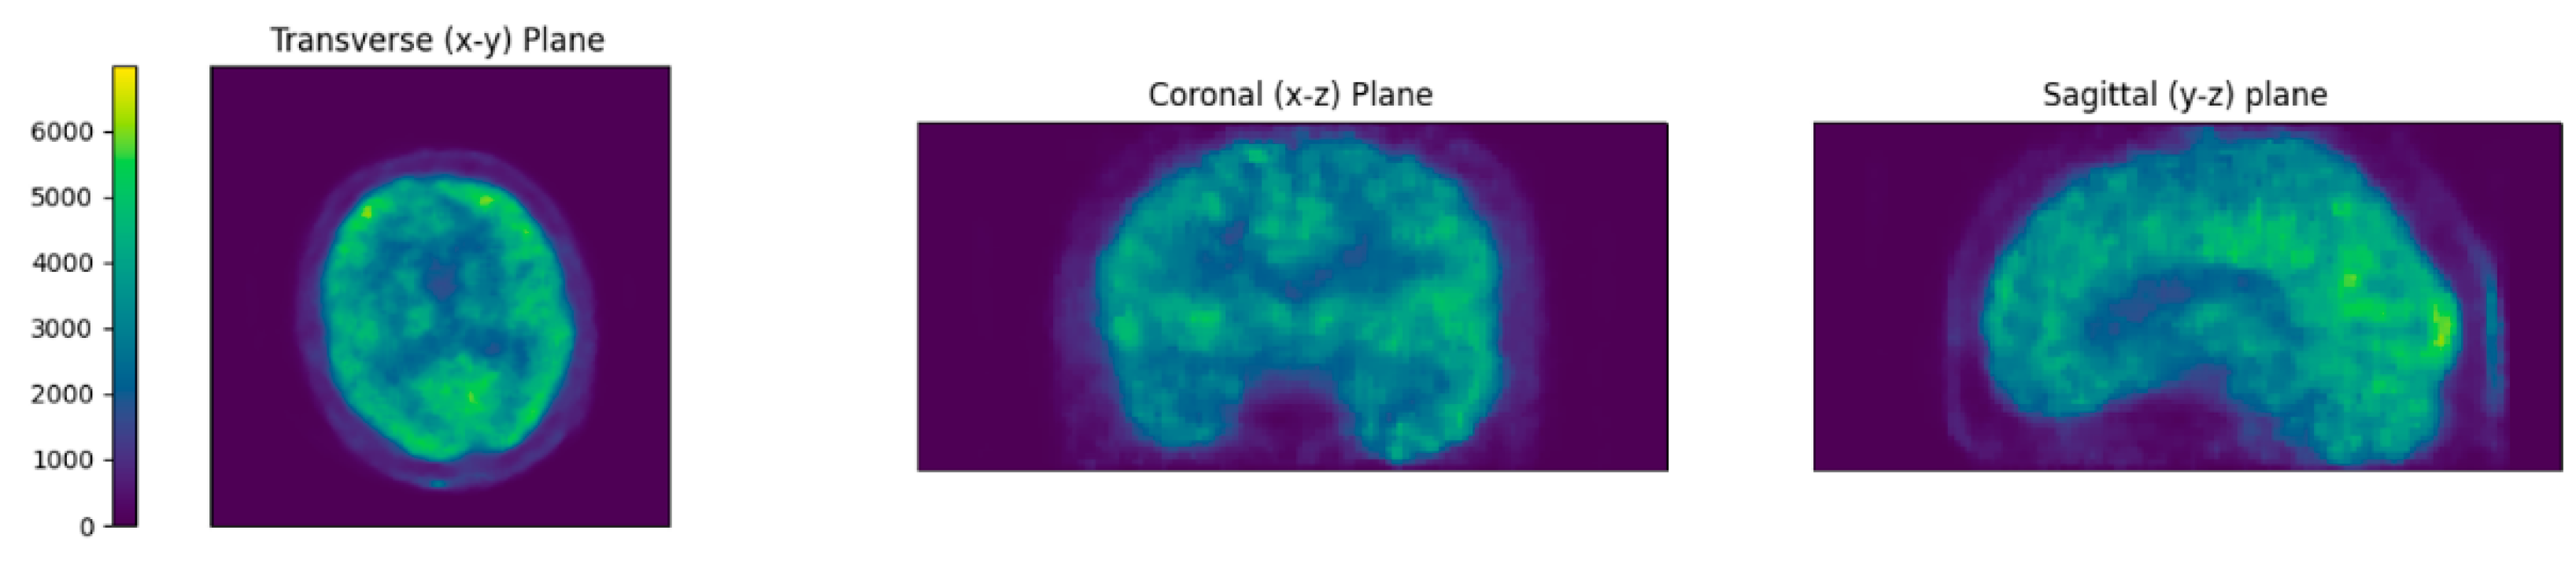

To assess the quality of the reconstructed BPET images, we compared them to the reference PET scans obtained with the full-body PET/CT system prior to the BPET data acquisition. This was done by comparing the relative voxel intensities in a collection of 67 volumes of interest (VOIs) defined on the AAL Merged Atlas [22,23]. For this, we exported the PET (“SPM5 derived PET template”) and VOI atlas (“AAL Merged Atlas”) images (Figure 3) from PMOD (PMOD Technologies, Zürich, Switzerland), and registered the BPET and the reference PET image to the PMOD PET atlas using the affine implementation of reg_aladin. Then, the PMOD VOI atlas was used to index the VOIs in the BPET and reference PET images to compute the average intensity within each VOI and divide it by the average intensity in the union of all VOIs. The reference PET images were smoothed with an isotropic 4.7 mm Gaussian 3D kernel (pre-registration), to approximately match the resolution of BPET which is between 4 mm and 9 mm, depending on the axial location [8]. The BPET images were filtered with a median filter with a kernel size of 5 × 5 × 5, to reduce salt and pepper noise observed in unfiltered reconstructions.

Figure 3.

The volumes of interest (VOIs) used for the image quality analysis, as defined in the AAL Merged Atlas in PMOD. Colors indicate discrete VOI numbering from 1 to 71 (with four indices not present).